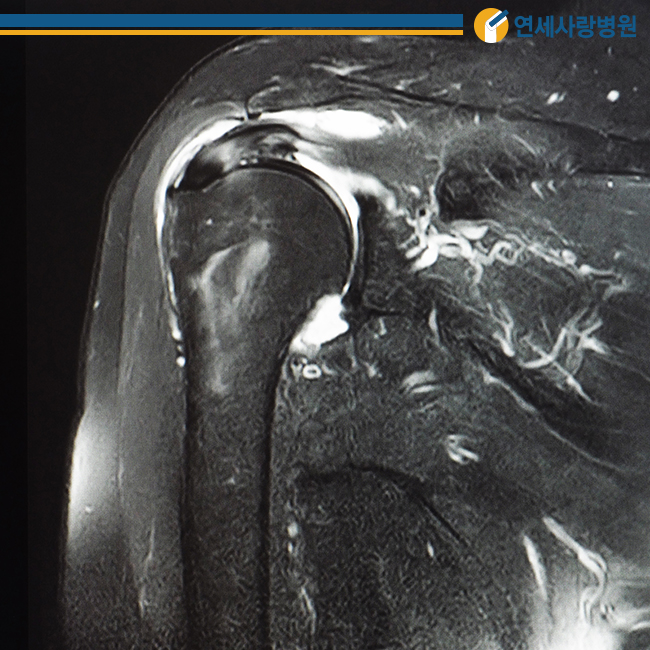

관절낭은 팔 윗부분과 어깨 관절을 얇게 감싸 움직임을 부드럽게 하는데 여러 가지 원인에 의해 염증이 생기면 관절낭 자체가 매우 두꺼워지고 힘줄과 인대가 유착되어 딱딱해집니다. 이 때 발생하는 통증을 가리켜 오십견이라고 합니다.

50대 전후에 다발하기 때문에 오십견이라고 불립니다만, 정확한 명칭은 동결견 또는 유착성 관절낭염이라고 합니다. 어깨를 움직이는 데 제한이 있을 뿐 아니라 어깨 관절을 움직이려고 해도 더 이상 움직일 수 없기 때문에 주의해야 합니다.